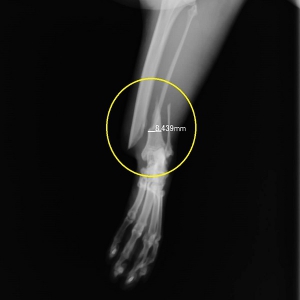

早速ですが、下写真が当院で撮影をやり直した骨折のレントゲン写真です。右写真が「スネの骨」側面から、左が正面像です。「くるぶし」のちょっと上に斜めに大きくずれた骨折が見られます。(黄色丸の中)

骨折は脛骨(スネの骨)の骨折とそのお隣の細い骨、腓骨の(骨が外に出ていない)単純骨折です。通常、腓骨は脛骨とともに折れますから、以下、まとめて脛骨骨折とします。

骨折の分類としては骨に対して斜めに骨折線が走る、斜骨折と言います。また、骨折部位が骨の端にあるため、部位的には「遠位端骨折」といいます。遠位端の斜骨折は整復の難しい骨折のひとつです。